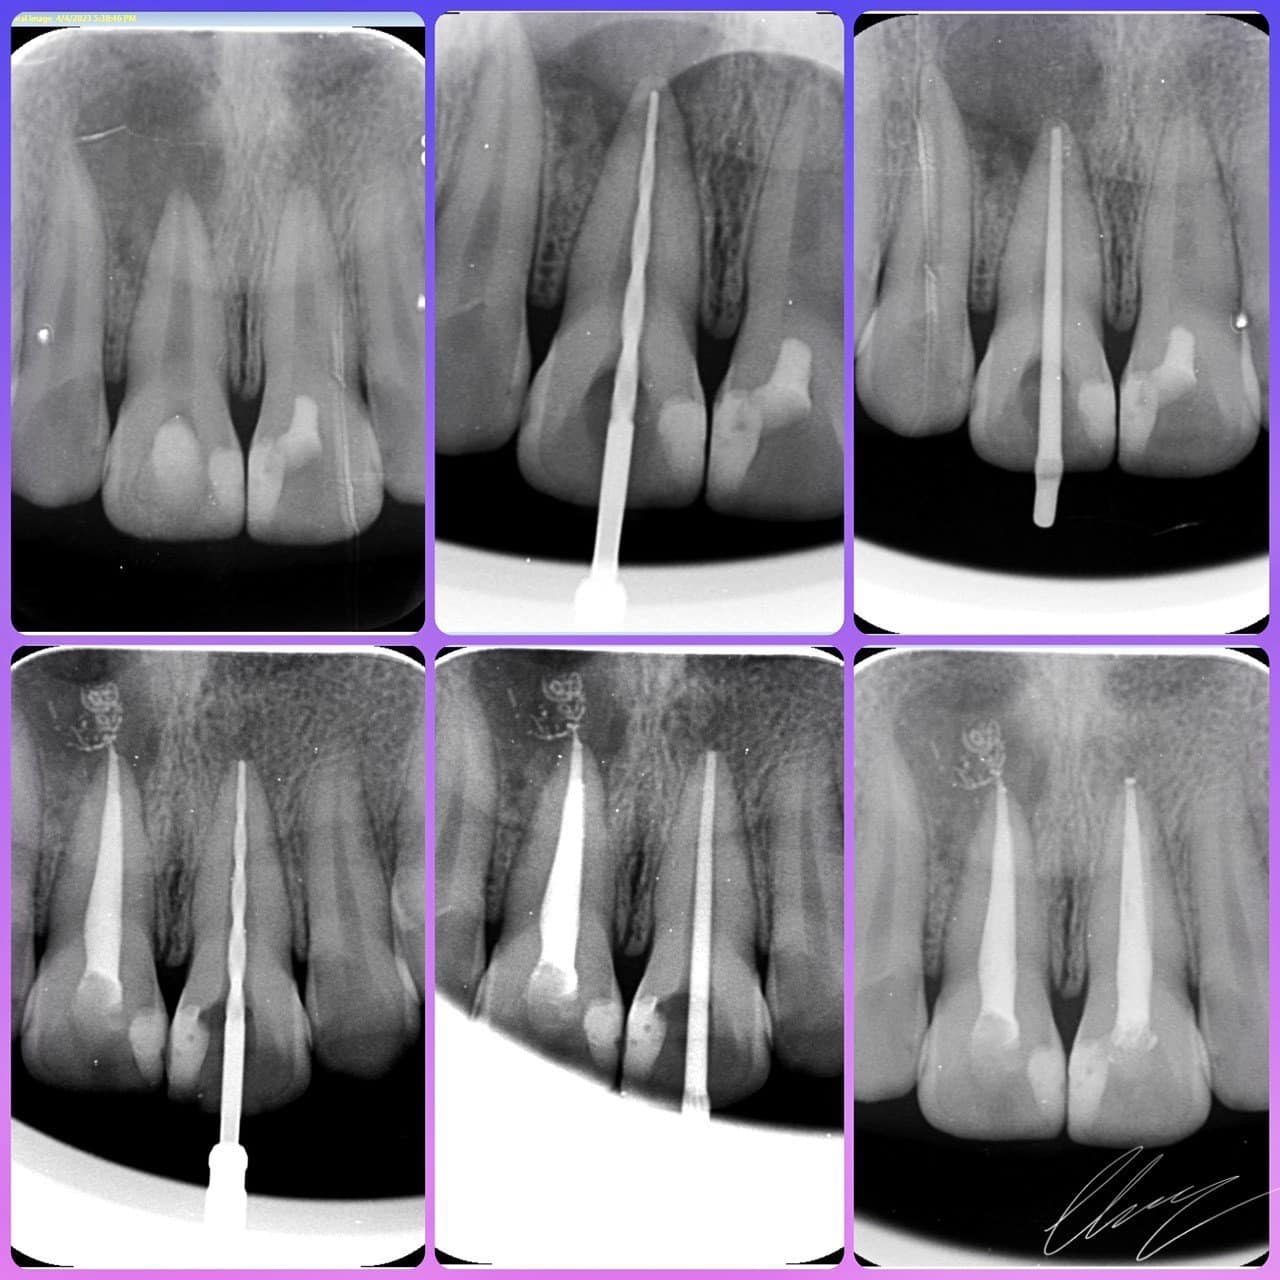

Điều trị tủy răng là phương pháp điều trị nội nha lấy bỏ tủy răng - một mô nhỏ dạng sợi ở chính giữa răng, sau khi lấy hết mô tủy bị hủy hoại, bị viêm hay bị chết tủy, khoảng trống trong ống tủy sẽ được làm sạch tạo thành ống tủy và sẽ được hàn kín lại bằng chất hàn nha khoa.

Điều trị tủy răng là một trong những điều trị cơ bản và quan trọng nhất trong nha Khoa. Mục Đích của điều trị tủy răng là giải phóng cơn đau, trả lại trạng thái không viên nhiễm cho răng, nhằm bảo tồn răng.